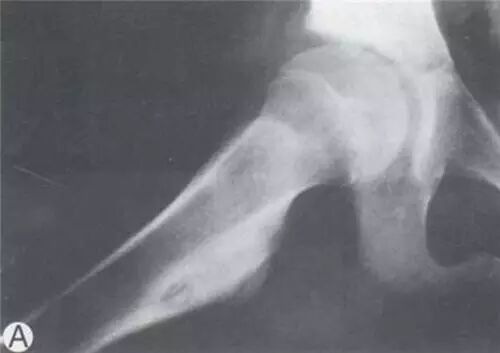

跖骨骨样骨瘤1例

【每周读片】骨样骨瘤

(骨样骨瘤)